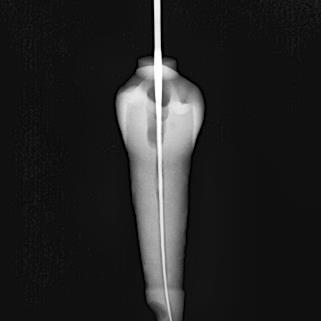

Se utilizaron 46 dientes extraídos unirradiculares superiores e inferiores con caries, pero sin compromiso radicular: sin ápices abiertos Los dientes con reabsorción radicular, fractura apical, caries que comprometieralaraízyápicesabiertosfueron descartados. Cada diente fue sometido a un proceso de limpieza por medio de ultrasonido para la remoción de cálculo y restos de tejido periodontal. Se le asigno un número a cada dienteysetomóunafotografíainicial(Figura 1).

Figura 1

FotografíainicialdeOD#27

Fuente: Pérez V, Salinas L. 2022.

Conductometría aparente

Es una de las etapas para obtener una medida de longitud, mediante una radiografía dentoalveolar, que corresponde a la distancia desde el punto de referencia coronal hasta el ápice radiográfico, definido como la porción

más apical del diente en una radiografía.

(Figura 2)

Figura 2

Conductimetría aparentedeOD#27

Fuente: Pérez V, Salinas L. 2022

Conductometría real

Una vez que se realizó el acceso cameral de cada uno de los dientes, se procedióatomarunaradiografíaconunalima 15, finalmente se tomó una radiografía para determinar la conductometría real. (Figura 3)

Figura 3.

ConductometríarealdeOD#27